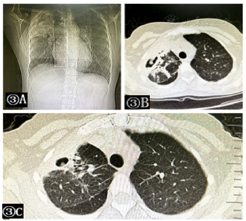

胸片(图3A):双肺多发斑片状阴影,右肺上叶可疑空洞形成。胸部CT检查(图3B):双肺多发片状及斑片状阴影伴空洞形成,病灶较前略吸收,炎性病变,结核不除外,左肺上叶陈旧性结核。2020年12月24复查胸部CT明显吸收(图3C)。

5.辅助检查(investigation,I)为病情需要,嘱患者1周后于卫生院复查血常规、胸片、心脏彩超,如气短加重或检验、检查结果有异常,及时联系专科进行转诊。病程期间患者出现气短加重,伴咳嗽、咳痰,咳白色泡沫样痰,2020年12月1日于卫生院查血常规未见明显异常。胸片提示双肺多发斑片状阴影,右肺上叶可疑空洞形成(图3A)。考虑患者肺空洞未见明显吸收。及时与患者及家属沟通病情情况,如下患者肺部感染是诊断明确的,近日症状明显,提示病情加重,其次引起肺空洞的疾病有很多:(1)细菌性肺炎。早期细菌性肺炎与肺脓肿在症状和X线片表现很相似,但常见的肺炎链球菌肺炎多伴有口唇疱疹、铁锈色痰而无大量脓臭痰,X线片显示肺叶或段性实变或呈片状阴影,没有空洞形成。(2)空洞性肺结核并发感染。空洞型肺结核是一种慢性病,起病缓慢,病程长,可长期咳嗽,午后低热、乏力、盗汗、食欲减退或有反复咯血。X线片空洞较厚,一般无气液平,痰中可查到结核杆菌,当合并肺部感染时,可出现急性感染症状和咳大量脓臭痰。(3)支气管肺癌。对于40岁以上的患者如若出现同一部位反复感染,且抗菌药物治疗效果差时,可考虑该疾病,需要送痰液查癌细胞和支气管镜检查,以明确诊断。上述疾病如需明确诊断均要进一步完善相关检验、检查,卫生院条件不允许,患者既往于上级医院就诊时病情危重,目前出院1个月左右,胸片提示有空洞形成,需要进一步诊疗,患者及家属同意转诊。

6.随访、观察(observation,O)-Follow-up。2020年12月3日上级医院血常规等检验检查未见明显异常。结核杆菌抗体阳性;血沉35 mm/h。痰细菌培养铜绿假单胞菌,对左氧氟沙星耐药,对派拉西林/亚胺培南/庆大霉素/环丙沙星敏感。胸部CT检查(图3B):双肺多发片状及斑片状阴影伴空洞形成,病灶较前略吸收,炎性病变,结核不除外,左肺上叶陈旧性结核。心脏彩超与之前相比无明显变化,PASP 68.9 mmHg。外送干扰素及ppd实验阴性;支气管镜子检查提示右主支气管黏膜轻度充血,上叶尖段官腔轻度狭窄,气管镜可见范围内官腔通畅,未见新生物形成,于右上叶开口处行黏膜刷检,使用生理盐水灌洗后送检支气管镜肺泡灌洗液,支气管黏膜炎症;左主支气管黏膜轻度充血,气管镜可见范围内管腔通畅,未见新生物。肺泡灌洗液外送NGS提示铜绿假单胞菌,真菌、抗酸染色未见异常,积极给予派拉西林他咗巴坦静脉输液联合口服环丙沙星抗感染治疗,辅以化痰、解痉、平喘、保护胃黏膜等支持治疗后,患者神清、精神可、偶有咳嗽,无胸闷气短等不适,于2020年12月24复查胸部CT明显吸收(图3C),好转出院。